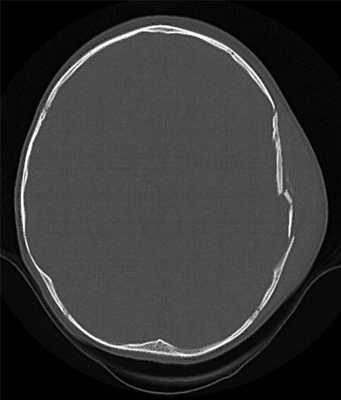

КТ позволяет последовательно изучить мягкие ткани головы, кости черепа, вещество мозга, эпидуральные, субдуральные, субарахноидальные пространства, цистерны основания и желудочки мозга:

- выявить переломы свода и основания черепа (с чувствительностью, намного превышающей традиционную рентгенографию) ,

Визуализация минимальных количеств излившейся свежей крови, уверенная дифференциация ее от других внеклеточных жидкостей, слежение за динамикой отека и набухания головного мозга, некроза и восстановления его структур с одновременным распознаванием переломов костей черепа, особенно его основания, составляют преимущества КТ перед магнитно-резонансной томографией.